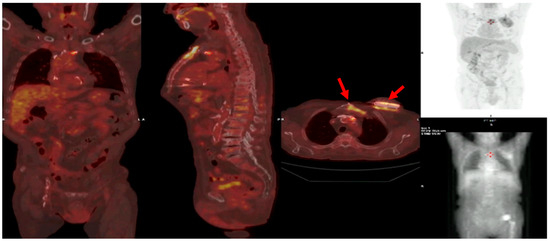

Multimodality Imaging in Infective Endocarditis: A Clinical Approach to Diagnosis

by Leonardo Brugiatelli, Francesca Patani, Carla Lofiego, Martina Benedetti, Irene Capodaglio, Pongetti Giulia, Francioni Matteo, Paolini Enrico, Nazziconi Marco, Kevin Maurizi, Furlani Giulia, Massari Arianna, Luciani Simone, Anselmi Benedetta, Gatti Chiara, Schicchi Nicolò, Fogante Marco, Tarsi Giovanni, Dello Russo Antonio, Di Eusanio Marco, Marini Marco and Fabio Vagnarelliadd Show full author list remove Hide full author list

Medicina 2025, 61(12), 2241; https://doi.org/10.3390/medicina61122241 - 18 Dec 2025

Infective endocarditis (IE) is a life-threatening condition with a rising incidence, demanding rapid and precise diagnosis. While echocardiography remains the cornerstone of initial evaluation, its limitations in complex cases—such as those involving prosthetic valves or cardiac devices—are well-known. This review synthesizes current evidence [...] Read more.

Infective endocarditis (IE) is a life-threatening condition with a rising incidence, demanding rapid and precise diagnosis. While echocardiography remains the cornerstone of initial evaluation, its limitations in complex cases—such as those involving prosthetic valves or cardiac devices—are well-known. This review synthesizes current evidence and guidelines to outline a practical, multimodality imaging approach for IE. We emphasize that integrating advanced techniques like cardiac computed tomography (CT) and [18F]-fluorodeoxyglucose positron emission tomography/computed tomography (FDG PET/CT) early in the diagnostic pathway, particularly in high-risk scenarios, significantly enhances diagnostic certainty, guides therapeutic decisions, and improves patient outcomes. A tailored imaging strategy, driven by clinical presentation and integrated within a multidisciplinary endocarditis team, is paramount for modern IE management. Full article

(This article belongs to the Special Issue Diagnosis and Treatment of Valvular Heart Diseases)

Show Figures

Figure 1